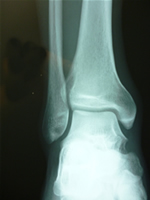

| 足の障害 | サッカー足・サイクリング足・足底筋膜炎・ 踵骨骨端症・捻挫 | 足関節捻挫・リスフラン関節・硬化症・外反母趾 |

| 下腿の障害 | アキレス腱炎・シンスプリント | アキレス腱炎・肉離れ |

ただし過度のスポーツや姿勢の異常で体に『負担を掛け過ぎると』軟骨や椎骨や各関節まで骨の変形が始まります。